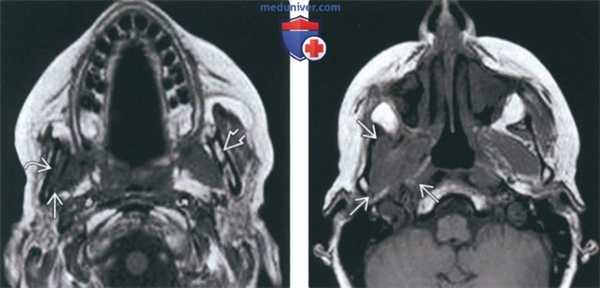

(Слева) Схема коронарной проекции, показана типичная злокачественная опухоль жевательного пространства, которая по волокнам нижнечелюстного нерва распространяется до овального отверстия и полости черепа.

(Справа) Пациент, у которого в анамнезе имеются сведения о пролеченном аде-нокисгозном раке щечного пространства. Онемение в области подбородка заставляет заподозрить рецидив опухоли и наличие периневральной инвазии. При МРТ Т1ВИ с КУ в коронарной проекции определяется опухоль, поражающая нижнечелюстной нерв в области жевательного пространства носоглотки. Опухоль проходит через овальное отверстие Я и начинает прорастать в тройничную полость. (Слева) МРТ Т1ВИ FS с КУ, аксиальная проекция, этот же пациент. Периневральное распространение опухоли в области нижнечелюстного отверстия. Обратите внимание, что с противоположной стороны накопление контраста минимальное. Однозначно, если рентгенолог целенаправленно не обращает внимание на этот признак, поставить правильный диагноз будет невозможно.

(Справа) МРТ Т1ВИ FS с КУ, аксиальная проекция, этот же пациент. Вокруг нижнечелюстного нерва, идущего в сторону овального отверстия, визуализируется опухолевая ткань, накапливающая контрастное вещество.

(Слева) На аксиальной МРТ (Т1 ВИ) у пациента, ранее пролеченного по поводу плоскоклеточного рака носоглотки, определяется замещение нормального жирового костного мозга в ветви нижней челюсти справа наряду с патологической мягкой тканью на уровне нижнечелюстного отверстия (ПНО ЧМН V3). Обратите внимание на нормальный гиперинтенсивный сигнал в жировом костном мозге в ветви нижней челюсти слева.

(Справа) На аксиальной МРТ (Т1 ВИ) у этого же пациента определяется ПНО ЧМН V3 с облитерацией жировых плааинок в жевательном пространстве.

(Слева) На корональной МРТ (Т1 ВИ С+) у этого же пациента определяется ПНО ЧМН V3 с распространением через овальное отвераиев меккелеву полость и кнаружи вдоль твердой оболочки в средней черепной ямке.

(Справа) На аксиальной КТ с КУ у этого же пациента визуализируется контрастирующаяся опухоль в нижнечелюстном отверстии справа наряду с патологическим контрастированием нижнечелюстной ветви V3 в жевательном пространстве.

(Слева) МРТ Т1ВИ в аксиальной проекции, пациент, которому ранее проводилось лечение по поводу плоскоклеточного рака носоглотки. Костный мозг в правой ветви нижней челюсти замещен опухолевой тканью, на уровне отверстия нижней челюсти также определяется патологическая ткань, появление которой связано с распространением опухоли по нижнечелюстному нерву. Обратите внимание на нормальный костный мозг левой ветви нижней челюсти, который имеет гиперинтенсивный сигнал.

(Справа) МРТ Т1ВИ в аксиальной проекции, этот же пациент. Периневральное распространение опухоли по нижнечелюстному нерву с облитерацией жировой клетчатки жевательного пространства.

(Слева) МРТ Т1ВИ с КУ, коронарная проекция, этот же пациент. По нижнечелюстному нерву опухоль распространяется в овальное отверстие и тройничную полость. Также опухоль прорастает латеральнее, в твердую мозговую оболочку средней черепной ямки.

(Справа) КТ с КУ в аксиальной проекции, этот же пациент. В области правого отверстия нижней челюсти определяется накапливающая контраст опухоль. В жевательном пространстве видны участки аномального накопления контраста вдоль волокон нижнечелюстного нерва.